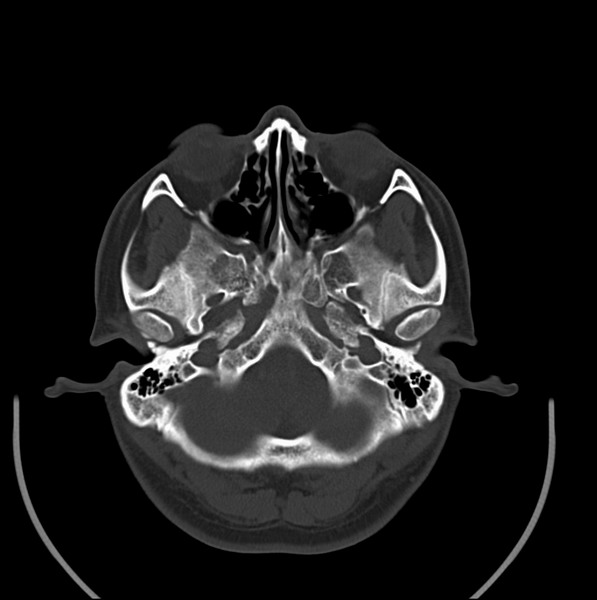

男、30、发现鼻咽部肿瘤侵犯海绵窦,未发现明显淋巴肿。请问国内那家医院治疗鼻咽部肿瘤最好?手术以何种方式为主?病灶可否全部切除?急切期待的大家的帮助。

扫描示鼻咽腔不对称,中度狭窄,右侧咽隐窝消失,局部软组织肿块,鼻咽右侧壁增厚形成肿块,突入鼻咽腔,肿块平扫呈等密度,肿块向深部侵润,右侧翼内外肌受侵,右侧咽旁间隙变窄;向后生长,头长肌界线欠清,向后上生长侵犯同侧颈动脉鞘区。双侧海绵窦增宽,内见软组织影与鼻咽部肿块相连。考虑鼻咽癌。鼻咽癌主要是放射治疗,且效果较好;到当地有治疗设备较大医院治疗即可。

这个病例有点特殊,和常见的鼻咽癌不太一样,以向颅内侵犯为主,骨质破坏区小。鼻咽癌首先要考虑,有没有其他可能?本人不会看mr片,期待有人能讲解,期待病理。